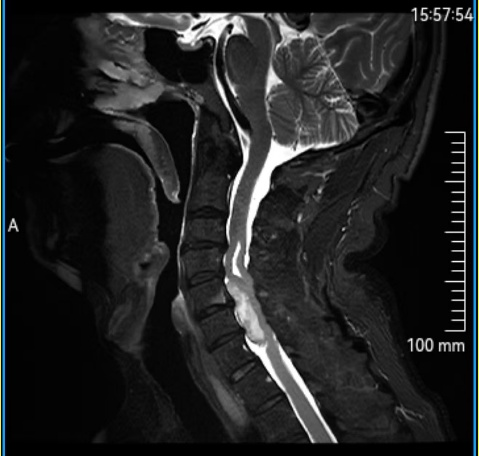

三个月前,55岁的王先生开始出现颈部僵硬、左腿无力、行走不稳等症状。经西安市红会医院颈椎病区系统检查,发现其颈椎椎管内有一个长约4厘米的肿瘤,严重压迫脊髓,导致神经功能进行性受损。

“肿瘤位于颈髓腹侧,与脊髓粘连紧密,手术操作空间狭小,稍有不慎即可能导致患者永久性瘫痪。”医生表示,颈椎管内本已空间有限,肿瘤进一步挤压脊髓,使其仅存薄薄一层,手术难度与风险极高。

手术当天,在3D显微镜的高清视野下,主刀医生开始了在“生命禁区”的精细操作。肿瘤与正常脊髓组织边界模糊,周围血管密布,每一步都需精准而谨慎。

“如同在豆腐上雕刻,既要彻底切除肿瘤,又必须保护脊髓不受损伤。”张永远医生这样形容。手术团队借助先进的3D显微镜与显微器械,细致分离肿瘤与脊髓组织,完整保留脊髓结构。历经近5小时的精细手术,肿瘤被彻底切除。术后第二天,王大爷左腿肌力明显恢复,行走稳定性显著改善,手术取得预期效果。